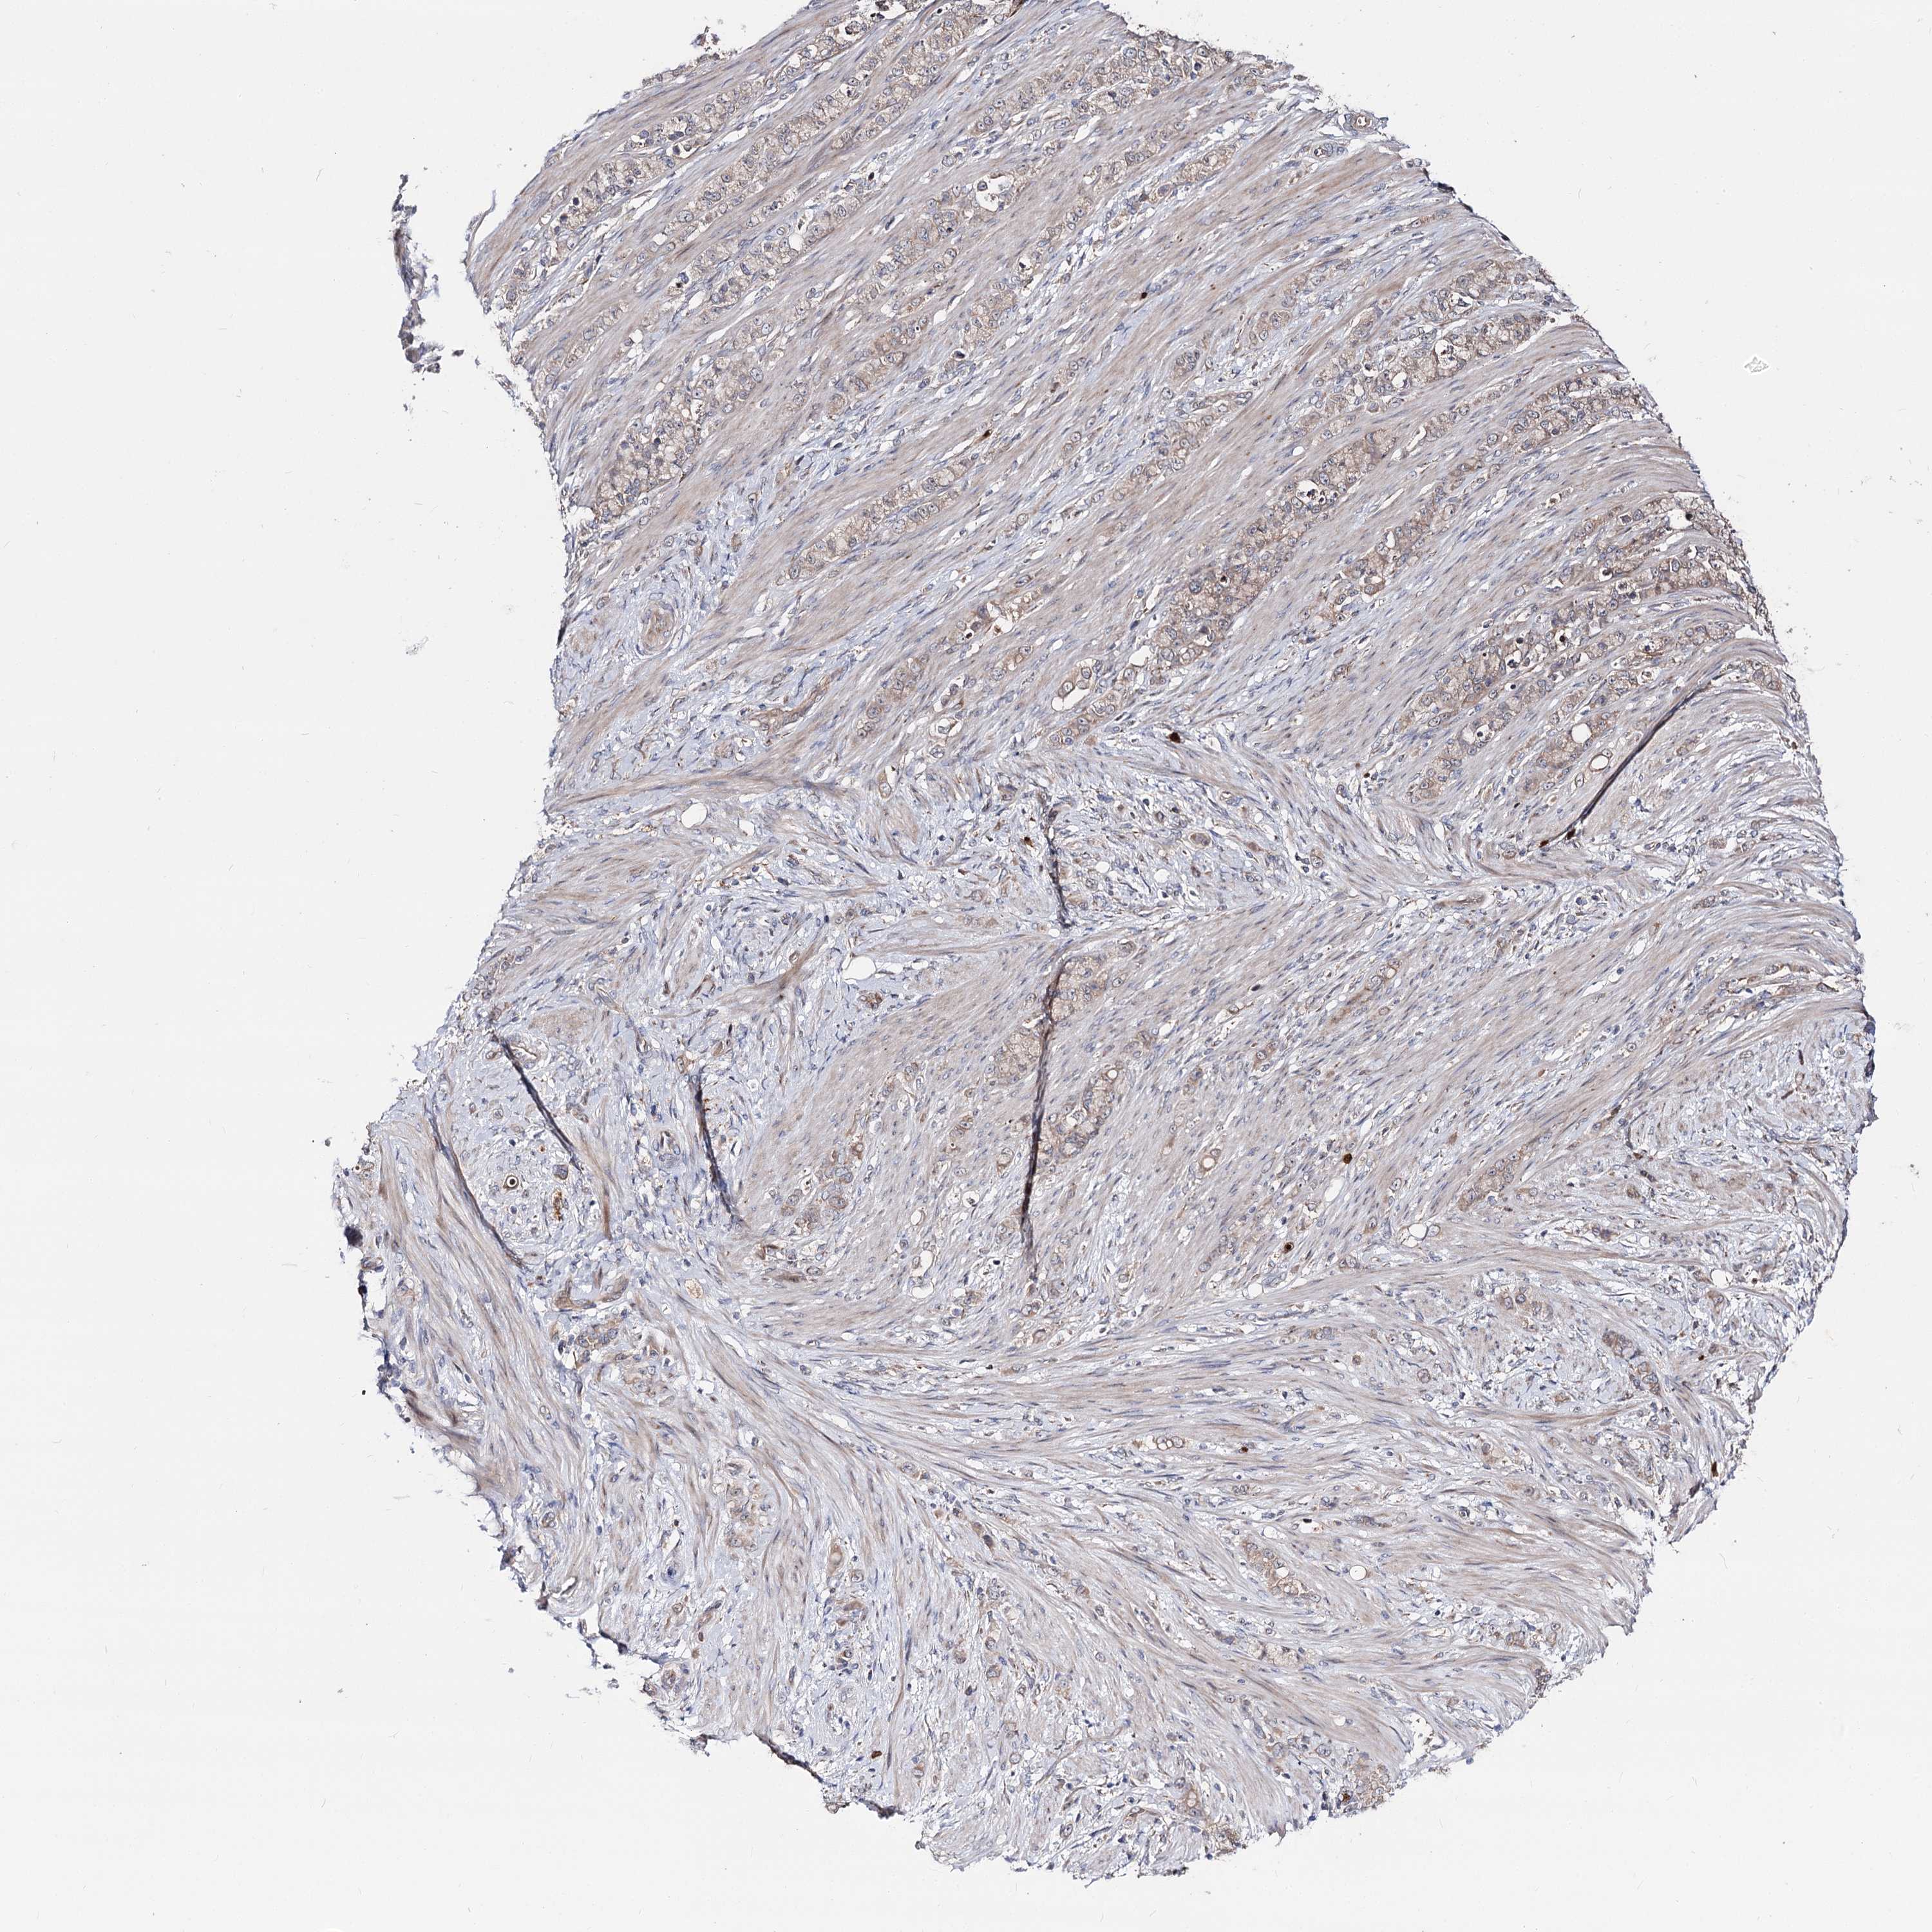

STOMACH CANCER - Protein expressioni

A mouse-over function shows sample information and annotation data. Click on an image to view it in a full screen mode. Samples can be filtered based on level of antibody staining by selecting one or several of the following categories: high, medium, low and not detected. The assay and annotation is described here.

Antibody stainingi

Antibody staining in the annotated cell types in the current human tissue is reported as not detected, low, medium, or high, based on conventional immunohistochemistry profiling in selected tissues. This score is based on the combination of the staining intensity and fraction of stained cells.

Each image is clickable and will lead to virtual microscopy that enables deeper exploration of all samples and also displays staining intensity scores, fraction scores and subcellular localization as well as patient and tissue information for each sample.

Antibody HPA038040

Staining

High

Medium

Low

Not detected

Intensity

Strong

Moderate

Weak

Negative

Quantity

>75%

75%-25%

<25%

None

Location

Nuclear

Cytoplasmic/membranous

Cytoplasmic/membranous,nuclear

Adenocarcinoma, NOS

Adenocarcinoma, High grade